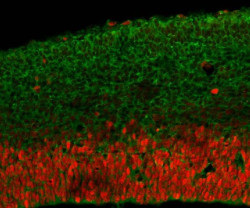

Un equipo internacional de investigadores del Centro de Investigación Hospitalaria de la Universidad de Montreal (CRCHUM), el Programa de Investigación Militar sobre el VIH de los Estados Unidos y el Centro de Investigación sobre el SIDA de la Cruz Roja Tailandesa ha demostrado que los primeros reservorios de VIH establecidos siguen siendo "sensibles" durante estas etapas tempranas y podrían reducirse unas 100 veces al iniciarse inmediatamente el tratamiento antirretroviral.